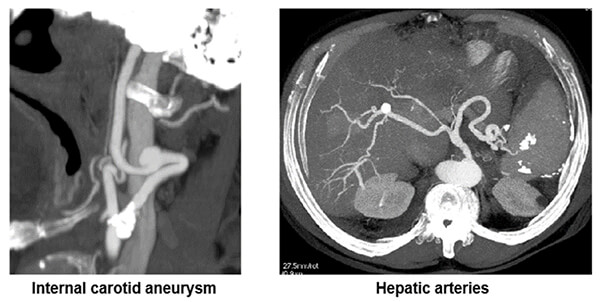

Vascular

Here an example of shows where the maximum intensity projection is used to search for vascular diseases or anomalies.

MIP Vascular: Renal Artery

This image shows us dysplastic renal artery stenosis. Notice the contour of the renal artery.